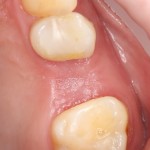

Через неделю можно снять швы. Область раны выглядит следующим образом:

А через два месяца — вот так:

На этом этапе, для создания более правильного десневого контура, можно поменять формирователь размер больше:

А еще через месяц — поставить временную коронку: